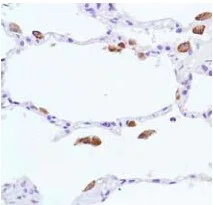

Formalin-fixed, paraffin-embedded human lung stained for iNOS using ab115819 at a dilution of 1/100 in immunohistochemical analysis.